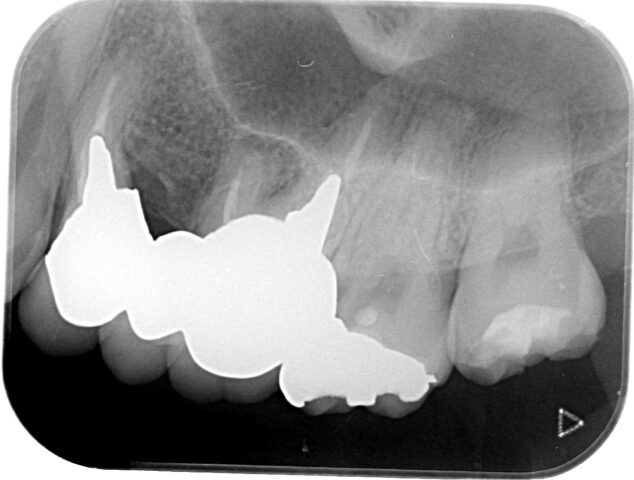

年齢 20代 性別 男性 主訴 今回の患者さんは、もともと定期検診にしっかりと通われていた意識の高い方でしたが、転勤に伴い当院へ初めて来院されました。「右上の歯が染みる」という症状があり、お口の中を拝見すると、一見しただけでは非常に小さな虫歯にしか見えません。

しかし、レントゲン検査を行うと、表面の小さな入り口とは裏腹に、内部で大きな空洞のように虫歯が広がっている像が確認されました。

患者さんには「見た目以上に虫歯が深く、治療の過程で神経に近くなる可能性があること」を事前に詳しくご説明し、可能な限り神経を残す方針で治療を開始しました治療 慎重に歯を削り進めていくと(Before/After写真参照)、やはり内部のカリエス(虫歯)は深く、神経のすぐ近くまで達していました。

通常の治療であれば神経を取る「抜髄(ばつずい)」を選択するケースも多い大きさでしたが、歯の寿命を延ばすためには神経の保存が不可欠です。そこで今回は、VPT(Vital Pulp Therapy:歯髄温存療法)を行いました。

精密な除去: マイクロスコープ(歯科用顕微鏡)を使用し、健康な組織を削りすぎないよう、感染部位のみを徹底的に除去。

MTAセメントによる封鎖: 生体親和性が高く、殺菌性・封鎖性に優れた「MTAセメント」を用いて神経を保護し、再感染を防ぐ処置を施しました。料金 4万円+税 備考 備考

本症例におけるVPTの適応および術式は、日本歯科保存学会のガイドライン、ならびに最新の臨床的エビデンスに基づき慎重に判断しています。

適応の判断: 術前の症状(自発痛の有無)やレントゲン診断、および術中の神経の露出状態や出血のコントロール具合を確認し、保存可能と診断したケースにのみ適用します。

リスクと経過観察: 処置後、一時的に痛みや違和感が出ることがありますが、経過観察を行い、神経の活性が維持されているかを定期的にチェックする必要があります。